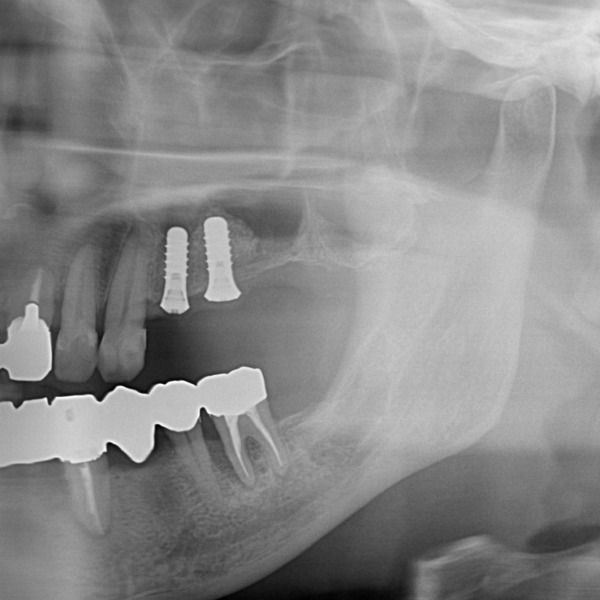

こちらが抜歯後、3ヶ月のレントゲン写真になります。

患者様は取り外しができる入れ歯ではなく、固定式のインプラント治療を希望されました。